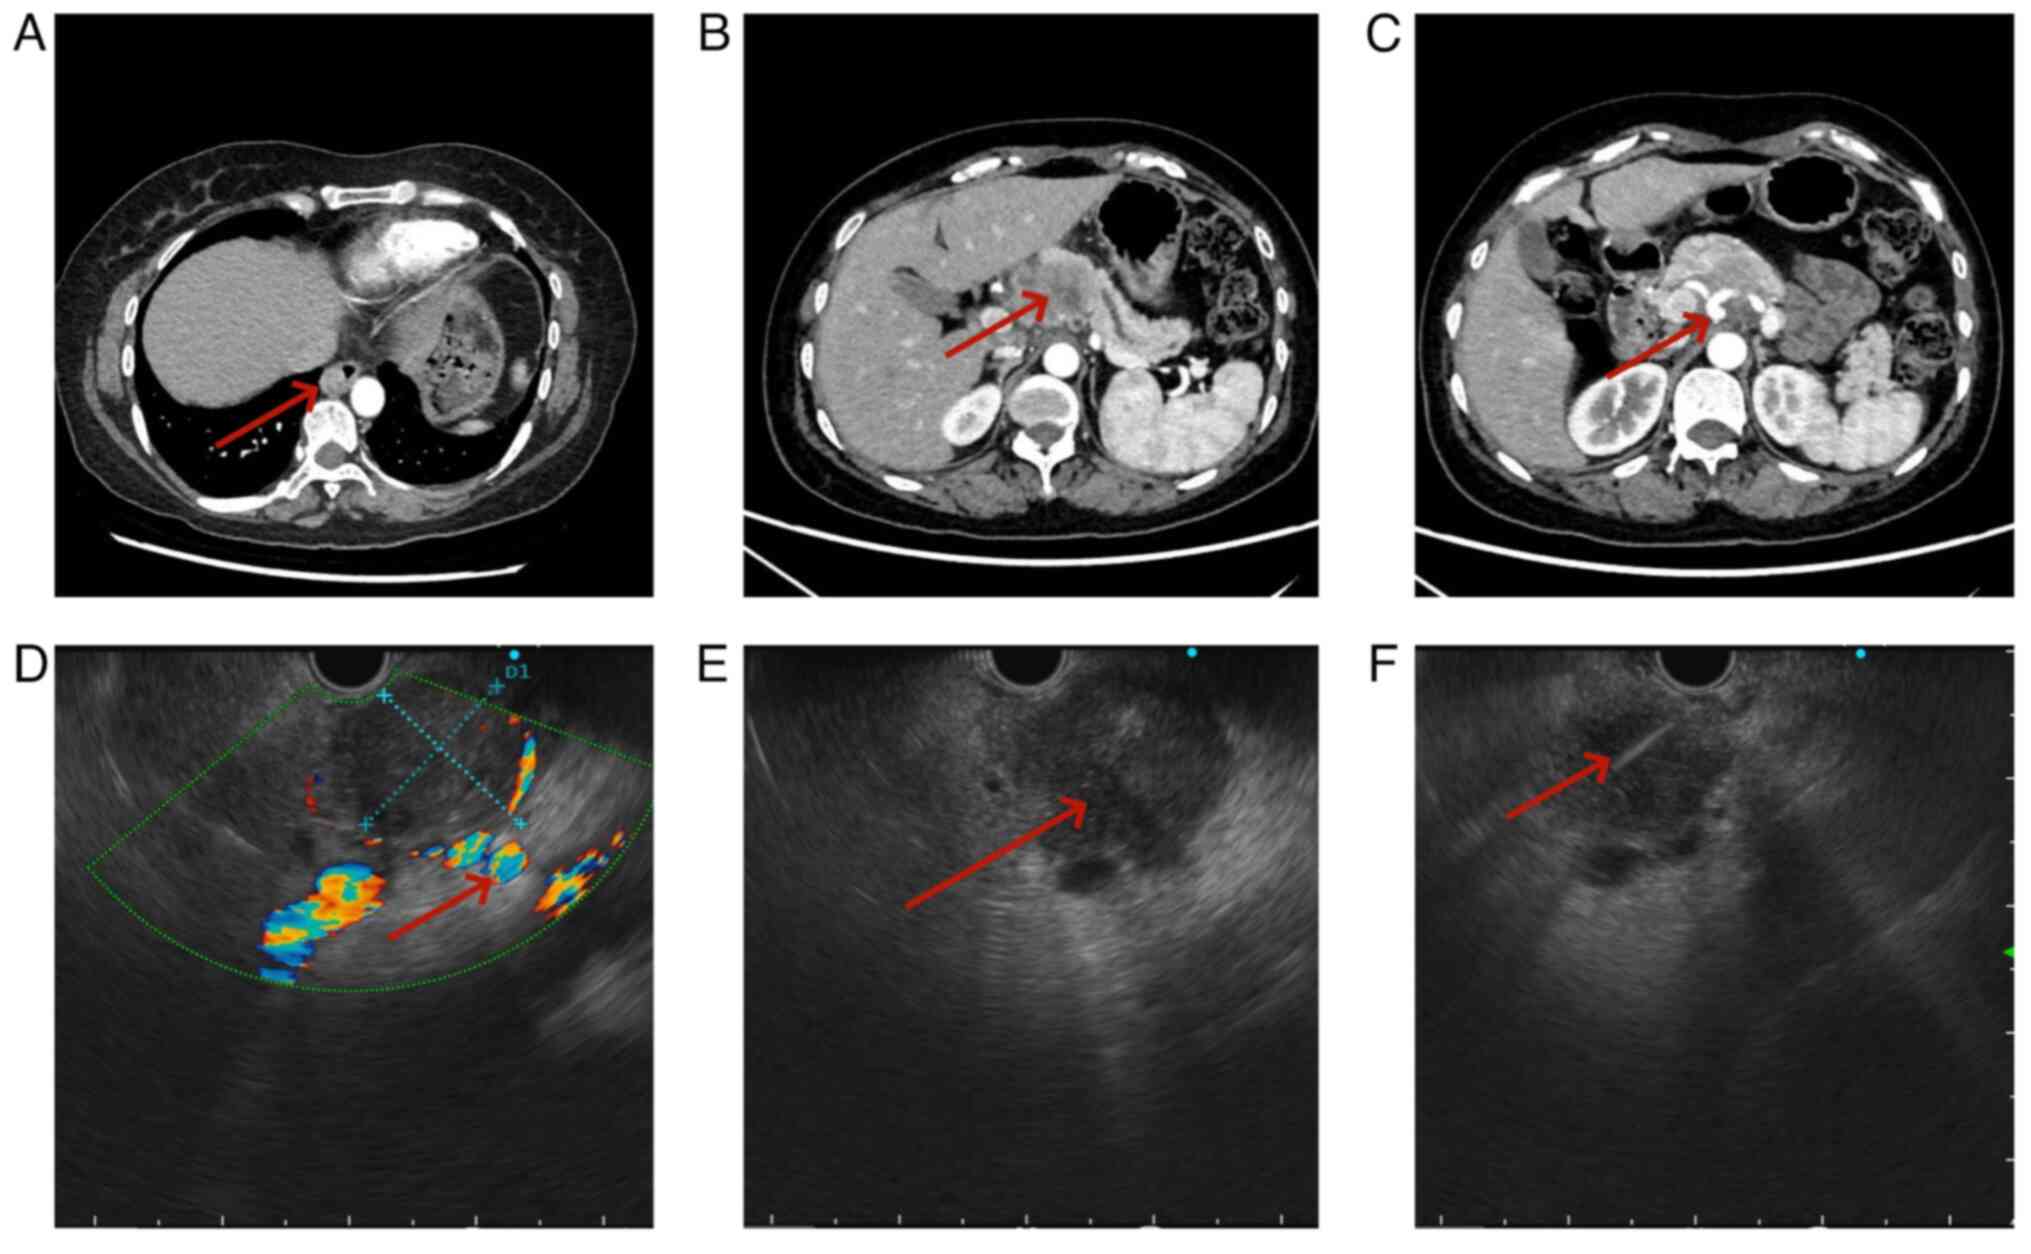

Figure 2.

Esophageal and pancreatic tumors on CT scans, as well as the characteristics of pancreatic tumors observed through EUS. (A) CT demonstrated a tumor in the distal esophagus (arrow), (B) CT demonstrated a tumor in the body of the pancreas (red arrow). (C) CT demonstrated the pancreatic tumor that invaded the splenic artery and common hepatic artery (red arrow). (D) EUS demonstrated a pancreatic tumor invading the splenic artery and the common hepatic artery (The red arrow indicates these arteries). (E) EUS demonstrated that the echo intensity of the tumor was low, and that the boundary between the tumor and surrounding pancreatic tissue was clear (red arrow). (F) EUS-FNA was performed to obtain pathological tissue of the pancreatic tumor. Arrow indicates the successful insertion of the 22G needle into the tumor, guided by endoscopic ultrasound). EUS-FNA, endoscopic ultrasound-guided fine-needle aspiration.

A 53-year-old female patient presented to Guangyuan Central Hospital (Sichuan, China) in March 2024 with dysphagia and epigastric pain that had lasted for 3 months, with no other accompanying symptoms. The patient underwent upper gastrointestinal endoscopy and pathological biopsy and was diagnosed with squamous cell carcinoma of the lower esophagus (Fig. 1A and B). The patient did not exhibit any other symptoms such as malnutrition, anemia or jaundice. The levels of carbohydrate antigen 19-9 and 125 in the blood test were 10.06 U/ml (normal range <37.00 U/ml) and 10.33 U/ml (normal range <35.00 U/ml), respectively. From a computed tomography (CT) scan (256-row GE Revolution CT, Revolution APEX; GE Healthcare; slice thickness was 1 mm) prior to surgery on March 2024, the thoracic surgeon identified a pancreatic tumor (Fig. 2A-C). Due to the potential of the tumor to infiltrate the celiac trunk vessels and multiple retroperitoneal lymph nodes, the multidisciplinary treatment (MDT) team opted to verify the pathological diagnosis of the tumor before proceeding with extensive multi-organ surgery. Subsequently, the patient underwent EUS scanning in April 2024, demonstrating a tumor measuring ~34.4×30.2 mm in the body of the pancreas. The echogenicity characteristics indicated that, in comparison with normal pancreatic tissue, there was a lower echo intensity with uniform punctate medium-high echoes present, which were slightly higher compared with that of the echoes observed in primary pancreatic cancer. The tumor exhibited clear demarcation from surrounding pancreatic tissue and invaded compression on the splenic and common hepatic artery. A few enlarged lymph nodes were observed in the retroperitoneum. Based on the EUS scan results, the initial determination of the tumor stage was uT4N1Mx. (According to the 8th American Joint Committee on Cancer TNM Staging of Pancreatic Cancer) (14). In April 2024, EUS-FNA was conducted on the tumor in the body of the pancreas, which resulted in retrieval of a notable number of cells and tissue (Fig. 2D-F). The pathologist initially did not consider the present case to be a metastatic tumor to the pancreas. However, components indicative of keratinization and intercellular bridges that were less consistent with common pancreatic adenocarcinoma were identified in cytological [hematoxylin and eosin (H&E) and Papanicolaou stained]and histological (H &E stained)sections. Due to the patient history of esophageal squamous cell carcinoma, immunohistochemistry was conducted to assist in diagnosis. P40 and P63 were positive, with a Ki67 proliferation index of 70% (data not shown), which confirmed metastasis of esophageal squamous cell carcinoma to the pancreas (Fig. 3A-F). Tissue was immersed in 10% neutral formalin at room temperature for >20 h, after which it was embedded in paraffin blocks. The paraffin blocks were sectioned to a thickness of 4 µm and baked at 60°C for 30-60 min. Paraffin sections were immersed in fresh xylene and descending ethanol solutions, respectively. The tissue was then rinsed with tap water and PBS and heated to 100°C. Following treatment with 3% H2O2 for 10 mins at room temperature, 10% normal goat serum (Scientific Phygene) was added at 37°C for 30 min to block nonspecific binding. Primary antibodies against Ki-67 (cat. no. SP6, 1:200, MXB biotechnologies), p63(MX013, 1:200, MXB biotechnologies), and p40 (MX048, 1:200, MXB biotechnologies) were added and incubated at 37°C for 2 h. The samples were then washed 3 times with PBS (2 mins). Subsequently, added horseradish peroxidase (HRP)-labeled goat anti-rabbit IgG as the secondary antibody (Everything Biotechnology Co, Hefei, China, BL003A) for P40 and Ki67, and HRP-labeled goat anti-mouse IgG as the secondary antibody (Everything Biotechnology Co, Hefei, China, BL001A; all 1:200 and incubated at 37°C for 30 mins. The samples were washed again 3 times with PBS with each wash lasting 2 mins. A volume of 10 µl freshly prepared DAB solution was added to the samples at room temperature for 5-8 min, samples were rinsed with tap water and counterstained with hematoxylin for 30-60 sec at room temperature, followed by rinsing with tap water to restore the blue color. The samples were dehydrated by using ethanol gradients. Sections were treated with xylene 3 times for 2 mins each to achieve transparency. Finally, the sections were sealed with neutral gum and observed under a light microscope (Olympus, Tokyo, Japan). The Papanicolaou staining was conducted as follows: Slides were immersed in 95% ethanol solution for a minimum of 15 mins at room temperature. Following washing with clean water 2 to 3 times, they were stained with hematoxylin dye. Once the coloration was clearly visible, the slides were rinsed with water. Subsequently, the slides were immersed in a lithium carbonate solution for 1 to 2 mins. After reverting to blue, the slides were rinsed with water and then transferred to a 95% ethanol solution for dehydration, allowing them to sit for 1 min to eliminate any excess water and immersed in orange G6 stain for 3 mins. Following this, they were immersed in 80, 95, and 95% ethanol solutions for 10 sec each. The samples were placed in EA36 solution followed by thorough rinsing with water. Finally, the samples were dehydrated using 95% ethanol 3 times and sealed with gum.